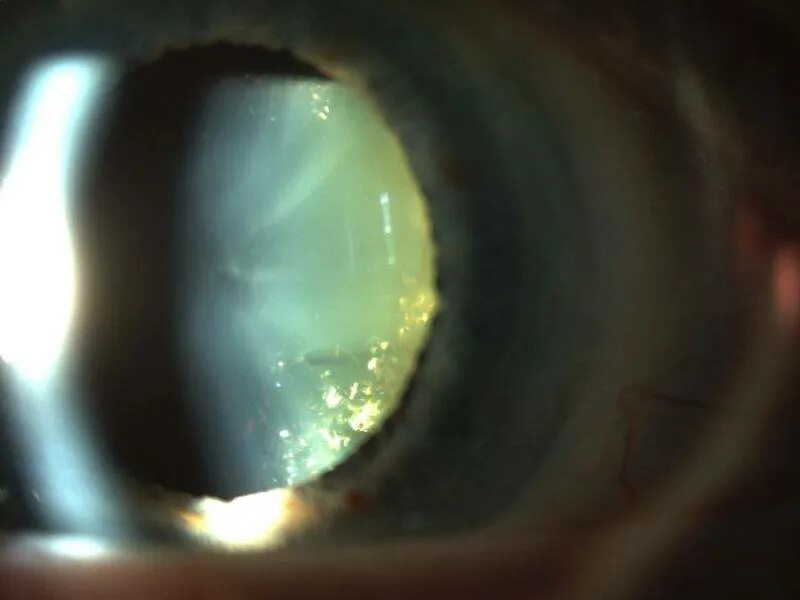

Можно заменить хрусталик повторно